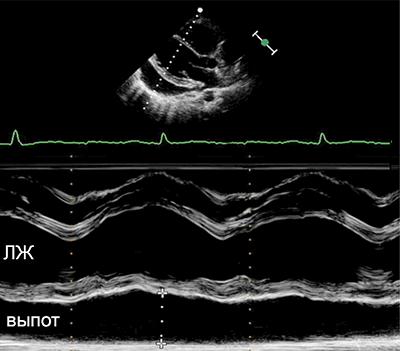

• Эхокардиография: выпот, утолщение перикарда.

• Выпот (>15–35 мл), сепарация эпикарда и перикарда >1 мм в диастолу.

• Величина выпота: малый (сепарация • Утолщение (>3–4 мм) и кальцификация перикарда (констриктивный перикардит).

• Эхокардиография: колебания сердца, выраженный выпот (>20 мм), диастолический коллапс камер сердца, аномальное движение МЖП, > вариабельности митрального потока (>25%) на вдохе.

• Выраженная сепарация эпикарда и перикарда >20 мм в диастолу на эхокардиограмме.